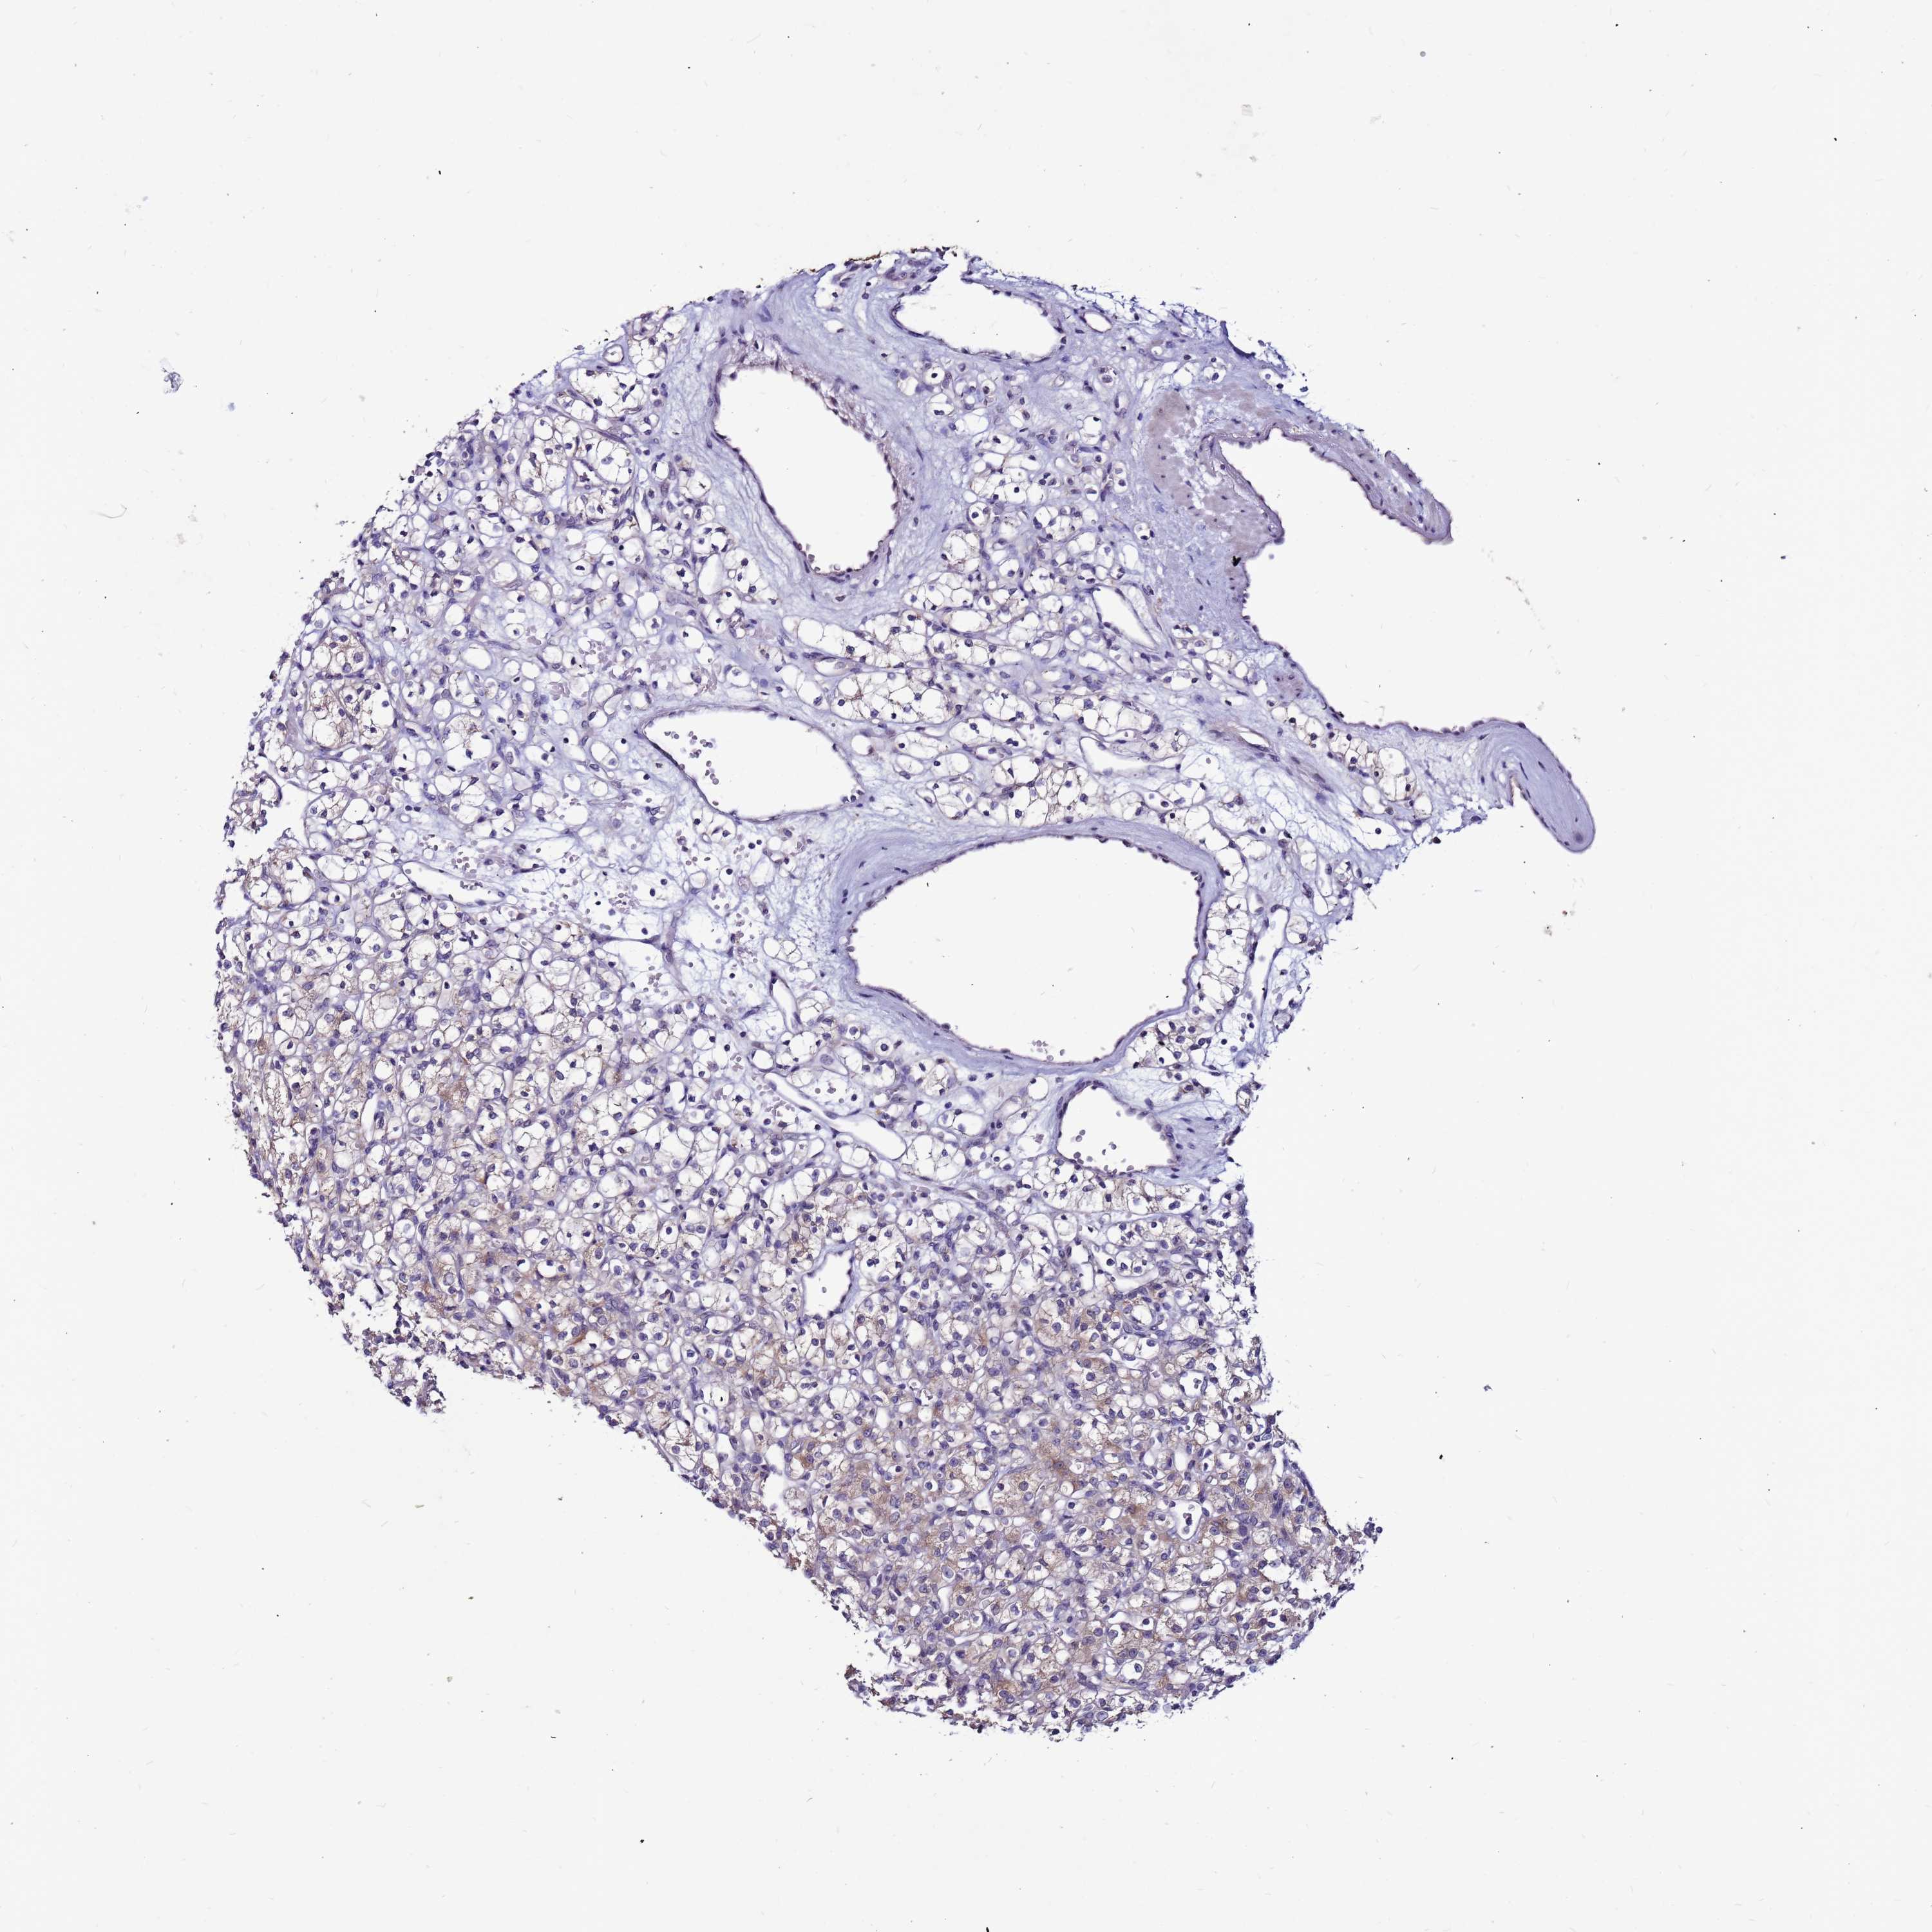

KIDNEY RENAL CLEAR CELL CARCINOMA (VALIDATION) - Interactive survival scatter ploti

The Survival Scatter plot shows the clinical status (i.e. dead or alive) for all individuals in the patient cohort, based on the same data that underlies the corresponding Kaplan-Meier plots. Patients that are alive at last time for follow-up are shown in blue and patients who have died during the study are shown in red.

The x-axis shows the expression levels (FPKM) of the investigated gene in the tumor tissue at the time of diagnosis. The y-axis shows the follow-up time after diagnosis (years). Both axes are complimented with kernel density curves demonstrating the data density over the axes. The top density plot shows the expression levels (FPKM) distribution among dead (red) and alive patients (blue). The right density plot shows the data density of the survived years of dead patients with high and low expression levels respectively, stratified using the cutoff indicated by the vertical dashed line through the Survival Scatter plot. This cutoff is automatically defined based on the FPKM cutoff that minimizes the p-score. The cutoff can be changed by dragging the vertical line or by entering a cutoff value in the square labeled "Current cut-off".

Under the Survival Scatter plot the p-score landscape (black curve; left axis) is shown together with dead median separation (red curve; right axis). Dead median separation is the difference in median mRNA expression between patients who have died with high and low expression, respectively. It is calculated as follows: median FPKM expression of dead patients with high expression - median FPKM expression of dead patients with low expression. This is intended to aid the user in visually exploring custom cutoffs and the associated p-scores and dead median separation.

Individual patient data is displayed and can be filtered by clicking on one or more of the category buttons on the top of the page. Categories describing expression level and patient information include: high, low, alive, dead, female, male and tumor stages. The scale of the x-axis can be toggled between linear and log-scale by clicking on the "x log" button. Mouse-over function shows TCGA ID, patient information and mRNA expression (FPKM) for each patient.

& Survival analysisi

Kaplan-Meier plots summarize results from analysis of correlation between mRNA expression level and patient survival. Patients were divided based on level of expression into one of the two groups "low" (under cut off) or "high" (over cut off). X-axis shows time for survival (years) and y-axis shows the probability of survival, where 1.0 corresponds to 100 percent.

SLC44A3 is not prognostic in Kidney Renal Clear Cell Carcinoma (validation)

: 29.55

Average pTPM 39.9

Number of samples 100